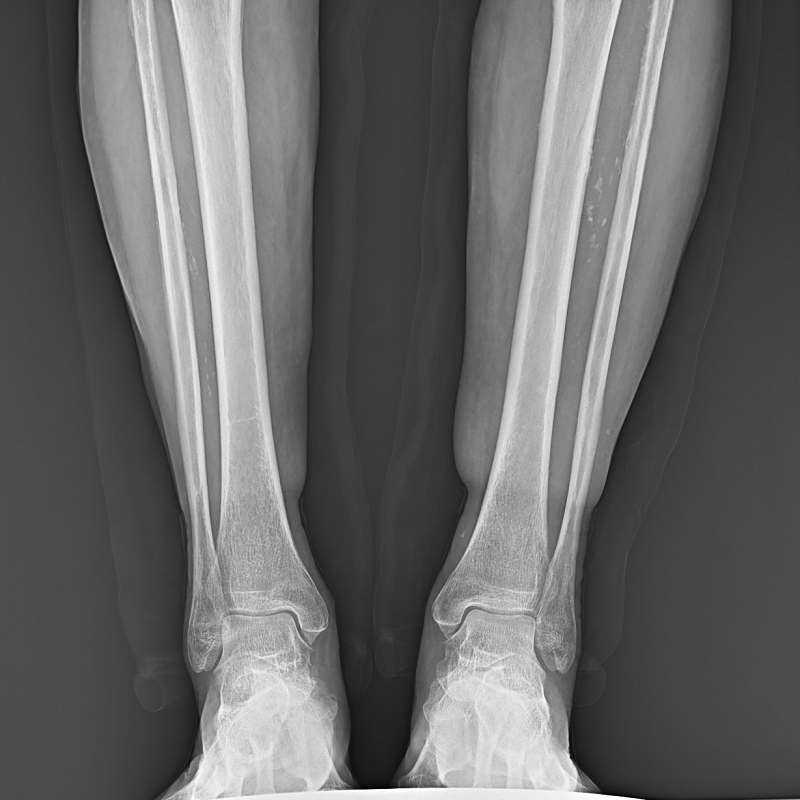

● 圖像拼接

系統(tǒng)可以識(shí)別曝光圖像,無需設(shè)置識(shí)別點(diǎn)即完成精準(zhǔn)拼接,呈現(xiàn)大范圍完整影像。